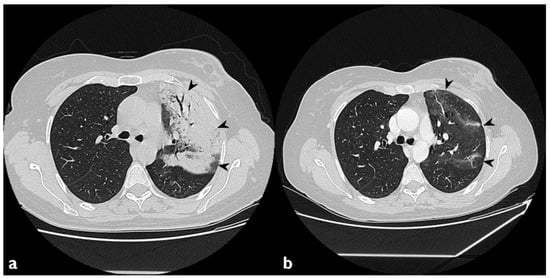

Figure 4. Atoll or reverse halo sign: areas of ground glass opacity surrounded by a ring- or a crescent-shaped consolidation (white arrowheads), which are clearly depicted in the right upper lobe (a) and in the right lower lobe (b).

1.3.2. Atoll Sign

The atoll sign (or reverse halo sign) was for a long time known to be pathognomonic of OP; in more detail, the term atoll was reported in literature in 1999 by Zompatori et al. [27], who described—in the cited paper—a ring-shaped opacity as a presentation of BOOP at HRCT. Actually, other conditions have been associated with this radiological feature: vasculitis, sarcoidosis with an atypical pattern, paracoccidiodomycosis, pneumocystis, tuberculosis, lipoid pneumonia and the complication of radio-frequency treatments. The atoll sign, however, has been classified among atypical patterns of COP, and it is related to the presence of an area of ground glass opacity surrounded by a ring-/crescent-shaped consolidation (Figure 4) [24,28,29].